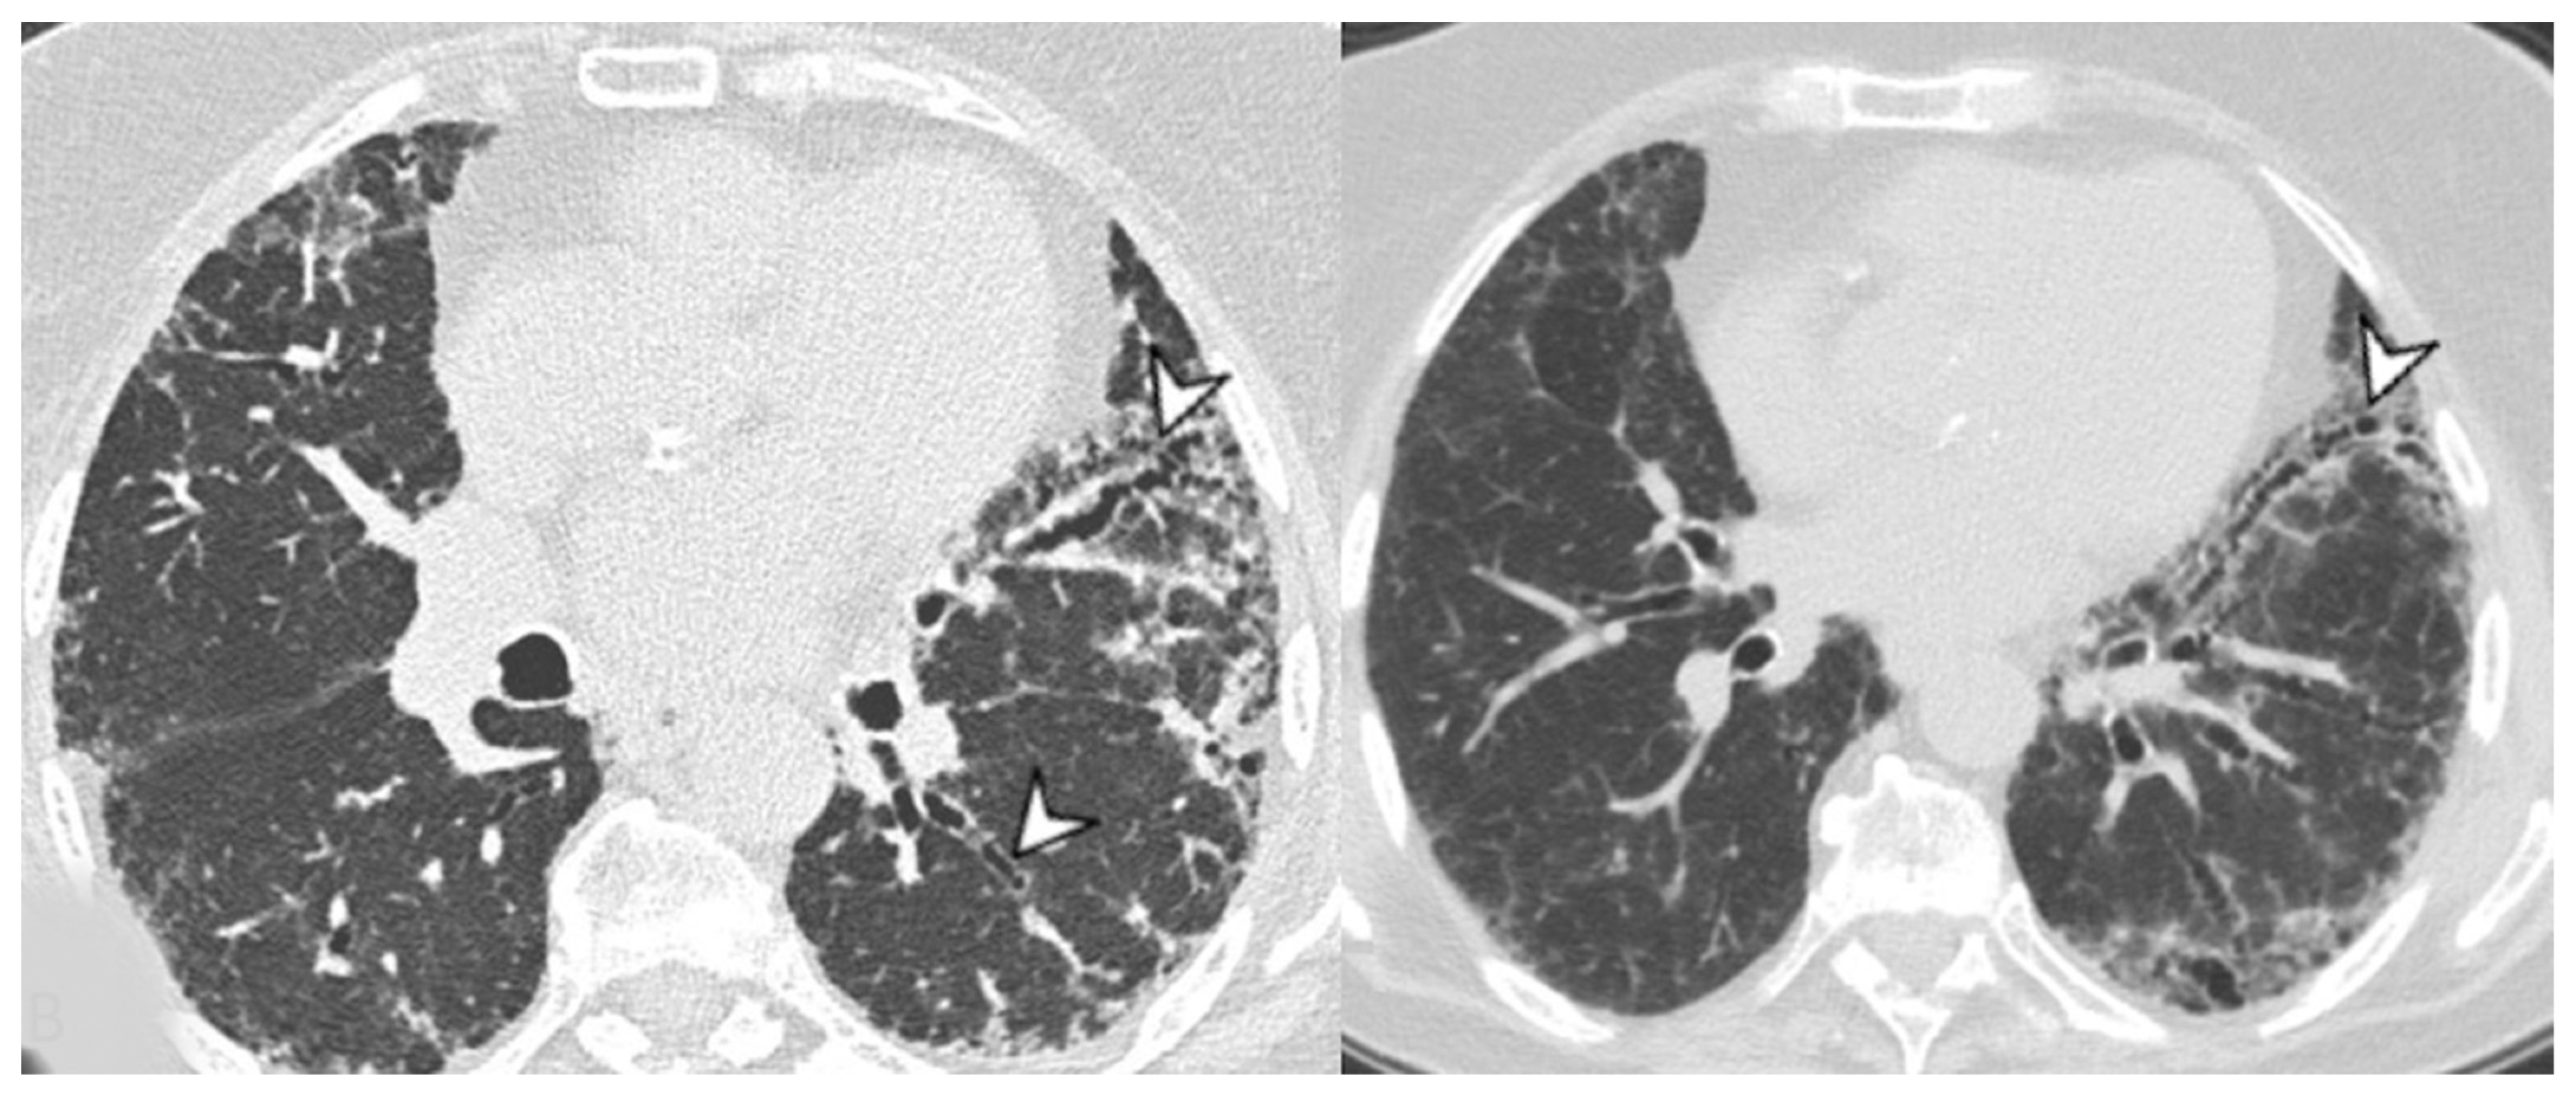

4.2.2. HRCT Findings of Patients with Anti-MDA-5 Abs

- Wu, W.; Guo, L.; Fu, Y.; Wang, K.; Zhang, D.; Xu, W.; Chen, Z.; Ye, S. Interstitial Lung Disease in Anti-MDA5 Positive Dermatomyositis. Clin. Rev. Allergy Immunol. 2021, 60, 293–304. [Google Scholar] [CrossRef]

| Lesions | GGO, reticulations, consolidations | consolidations, GGOs | |

| Distribution | Homogeneous; lower lung lobes, along bronchovascular bundles and lung periphery; loss of volume of lower lobes | Patchy; peripheral lower lobes or along the bronchovascular bundles | |

| CT pattern | NSIP OP NSIP-OP UIP DAD-unclassifiable | 50% 20% 25% 10% +/− | 20% 50% 25% <5% ++ |